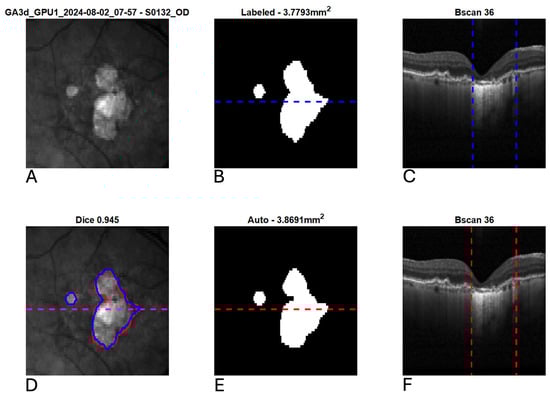

2.3. Deep Learning Architecture

2.4. Analysis Methods

3. Results